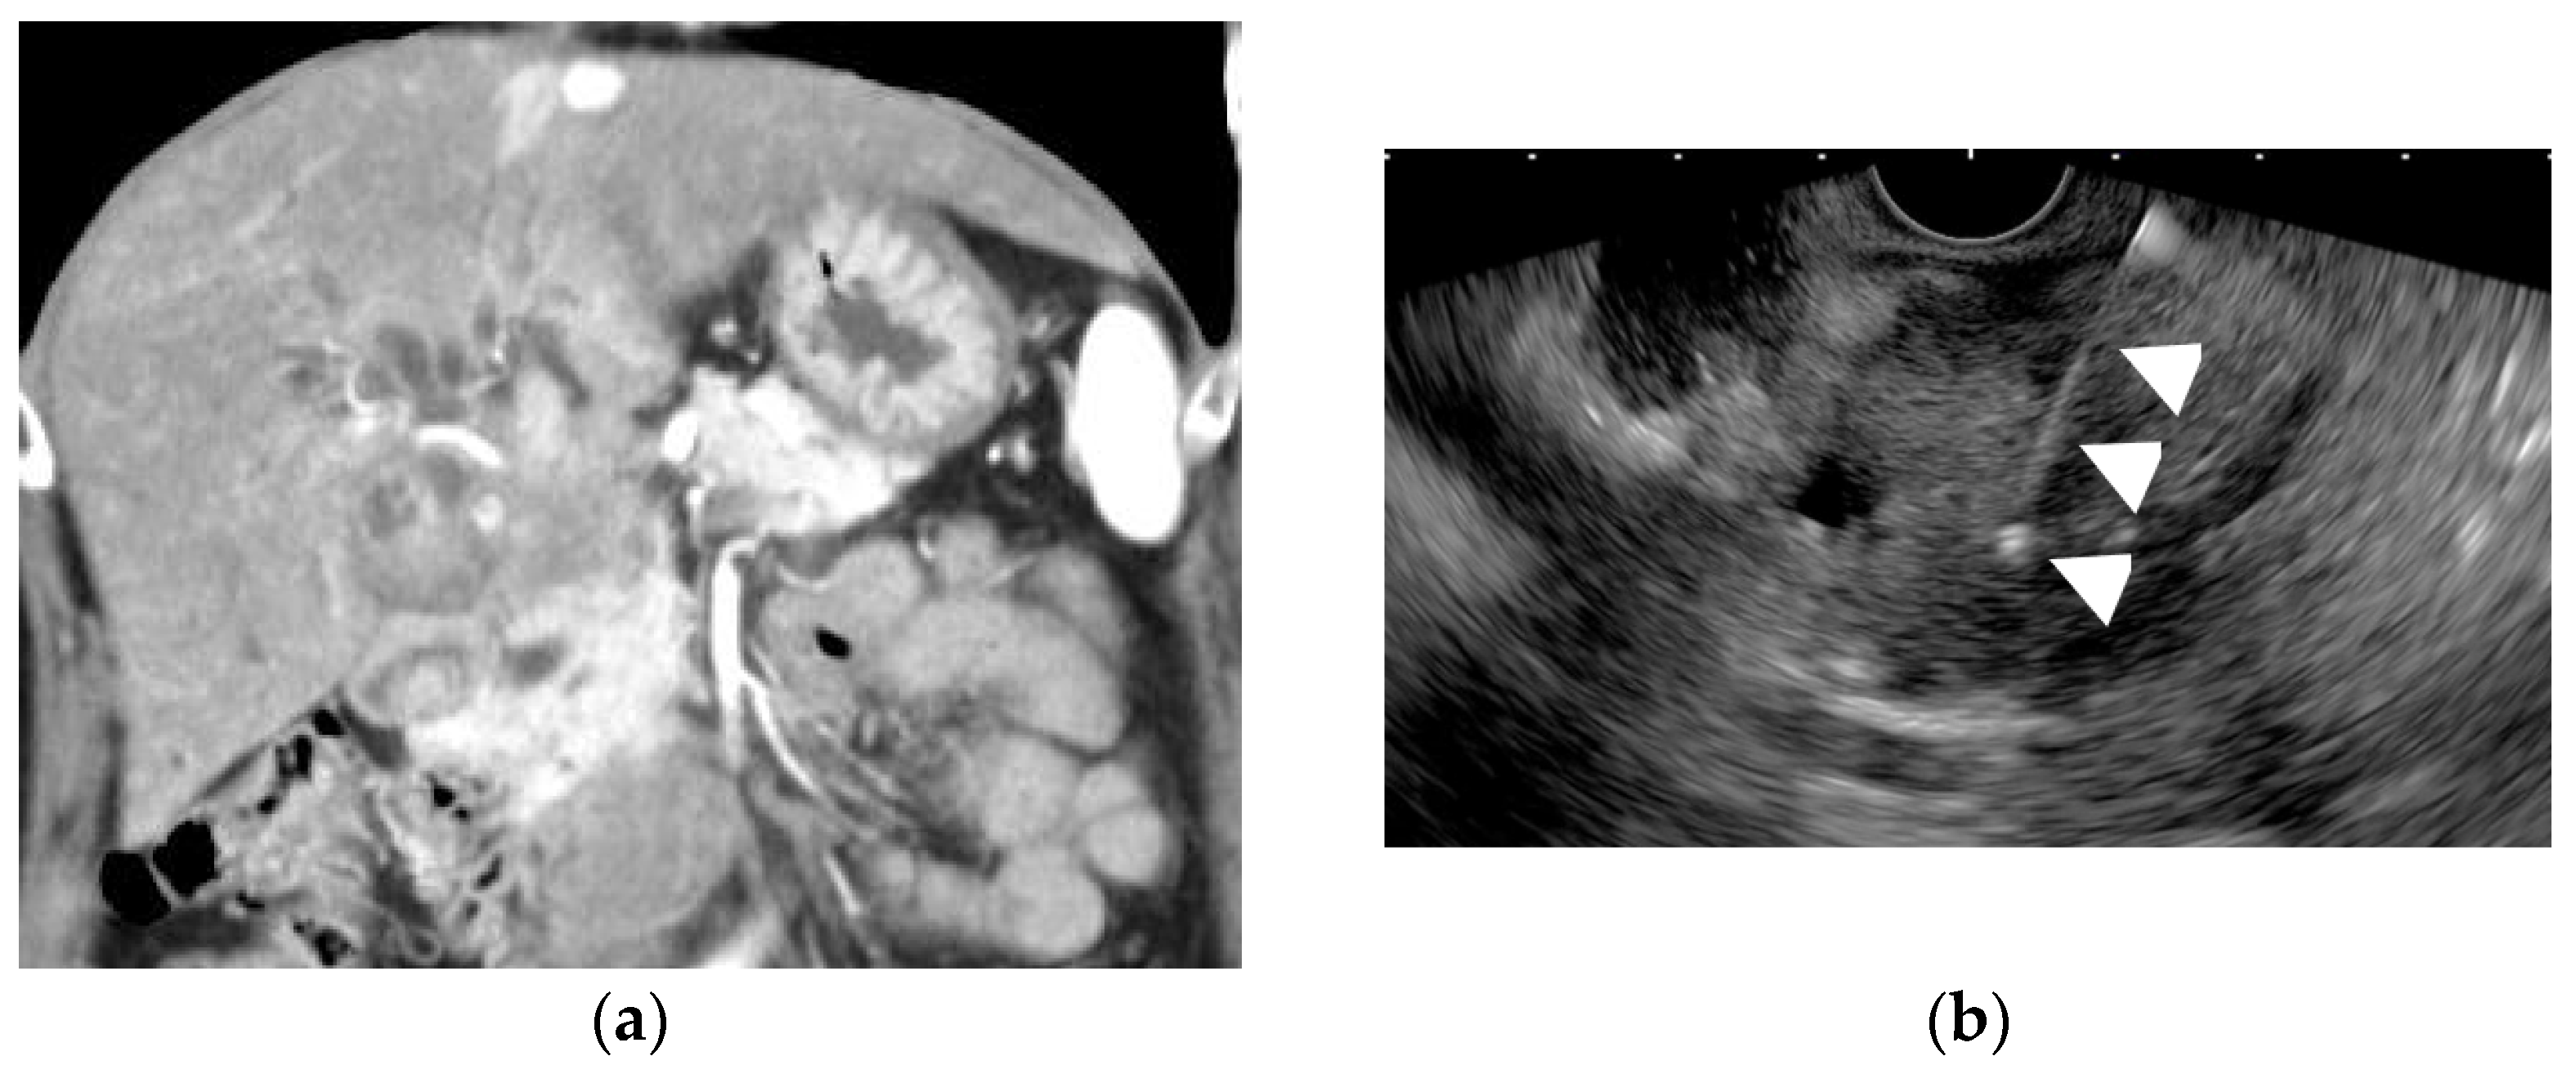

- Tanaka, K.; Katanuma, A.; Hayashi, T.; Kin, T.; Takahashi, K. Role of endoscopic ultrasound for gallbladder disease. J. Med. Ultrason. 2021, 48, 187–198. [Google Scholar] [CrossRef]

- Cho, J.H.; Park, J.Y.; Kim, Y.J.; Kim, H.M.; Kim, H.J.; Hong, S.P.; Park, S.W.; Chung, J.B.; Song, S.Y.; Bang, S. Hypoechoic foci on EUS are simple and strong predictive factors for neoplastic gallbladder polyps. Gastrointest. Endosc. 2009, 69, 1244–1250. [Google Scholar] [CrossRef]

- Lee, J.S.; Kim, J.H.; Kim, Y.J.; Ryu, J.K.; Kim, Y.T.; Lee, J.Y.; Han, J.K. Diagnostic accuracy of transabdominal high-resolution US for staging gallbladder cancer and differential diagnosis of neoplastic polyps compared with EUS. Eur. Radiol. 2017, 27. [Google Scholar] [CrossRef]

- Choi, J.H.; Seo, D.W.; Choi, J.H.; Park, D.H.; Lee, S.S.; Lee, S.K.; Kim, M.H. Utility of contrast-enhanced harmonic EUS in the diagnosis of malignant gallbladder polyps (with videos). Gastrointest. Endosc. 2013, 78, 484–493. [Google Scholar] [CrossRef] [PubMed]

- Kamata, K.; Takenaka, M.; Kitano, M.; Omoto, S.; Miyata, T.; Minaga, K.; Yamao, K.; Imai, H.; Sakurai, T.; Nishida, N.; et al. Contrast-enhanced harmonic endoscopic ultrasonography for differential diagnosis of localized gallbladder lesions. Dig. Endosc. 2018, 30, 98–106. [Google Scholar] [CrossRef] [Green Version]